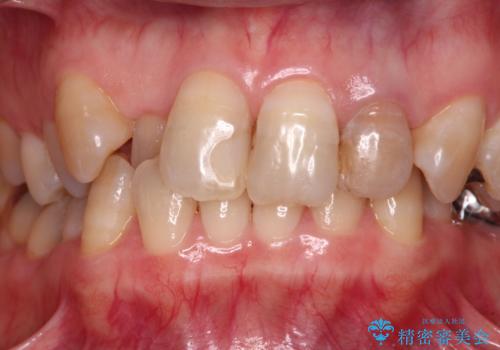

- 20年以上前に神経を取り除いた前歯の変色が気になるとのことで来院された患者様です。

レントゲン写真より、歯根の炎症が認められなかったため、ファイバーコアによる土台築製後、オールセラミッククラウンにて補綴することとしました。

また、真ん中の前歯はコンポジットレジンによる修復跡が目立っており、合わせてオールセラミッククラウンにて治療することとしました。

歯に独特の縞模様があり、さらに特徴的な色合いであったため、コンポジットレジンによる修復では対応が困難でした。